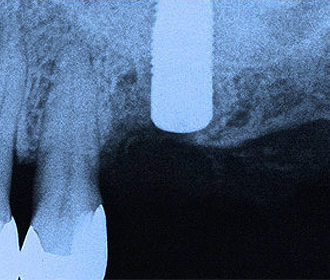

インプラント治療直後のレントゲン写真。

網目状のものがチタンメッシュ、ピンで骨に固定。 -